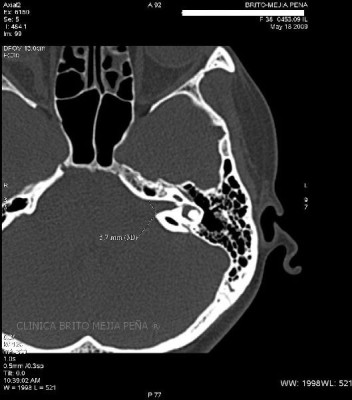

Envíado por BMP Imágenes Diagnósticas

BMP Imágenes Diagnósticas